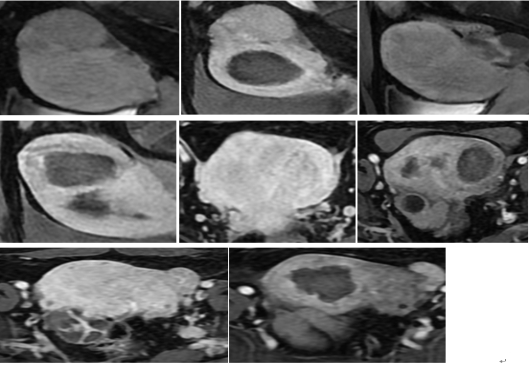

林女士12年前在省城医院行腹腔镜肌瘤剔除术,术后痛经症状缓解,未定期复查1年前检查发现“子宫肌瘤”,1个多月前以及2019年12月初多次彩超复查均提示:子宫增大、子宫壁低回声结节及团块,疑肌瘤最大约4.6x4.1cm的低回声结节,左侧卵巢囊肿3.4x2.7cm,达到手术指征

海扶,即高强度超声聚焦治疗(HIFU )。该技术利用超声波的非射线性、良好的组织内聚焦性和能量的可渗透性特点,利用较弱的超声源,与太阳在焦点处产生巨大能量原理相似,通过准确聚焦靶组织(肿瘤)产生的瞬态高温效应和空化效应,使肿瘤组织产生凝固性坏死,从而达到缩小和稳定肿瘤的目的。它是一种非侵入性消融治疗技术,无需手术切口及穿刺,是一种不侵入机体、不开刀、不流血的治疗方法,保留了患者生理功能,不影响日常生活。研究证明,HIFU治疗子宫肌瘤的有效性不劣于传统手术,而安全性优于传统手术,且能显著提高患者生活质量,缩短住院时间,节省医疗成本。

临床中已成熟应用20多年,三年多来,我院海扶治疗中心对子宫肌瘤、子宫腺肌症、子宫腺肌瘤、腹壁切口异位结节、切口妊娠、胎盘植入等多种疾病近千例患者进行了“无创治疗”,疗效均满意,无严重并发症发生。此项技术的成功应用,扩展了市第一人民医院妇科良性肿瘤的治疗方式,为本地区乃至川陕甘毗邻地区的妇科肿瘤患者提供了无创、无痛的高水平医疗服务,最大限度减少了患者的伤害和痛苦。